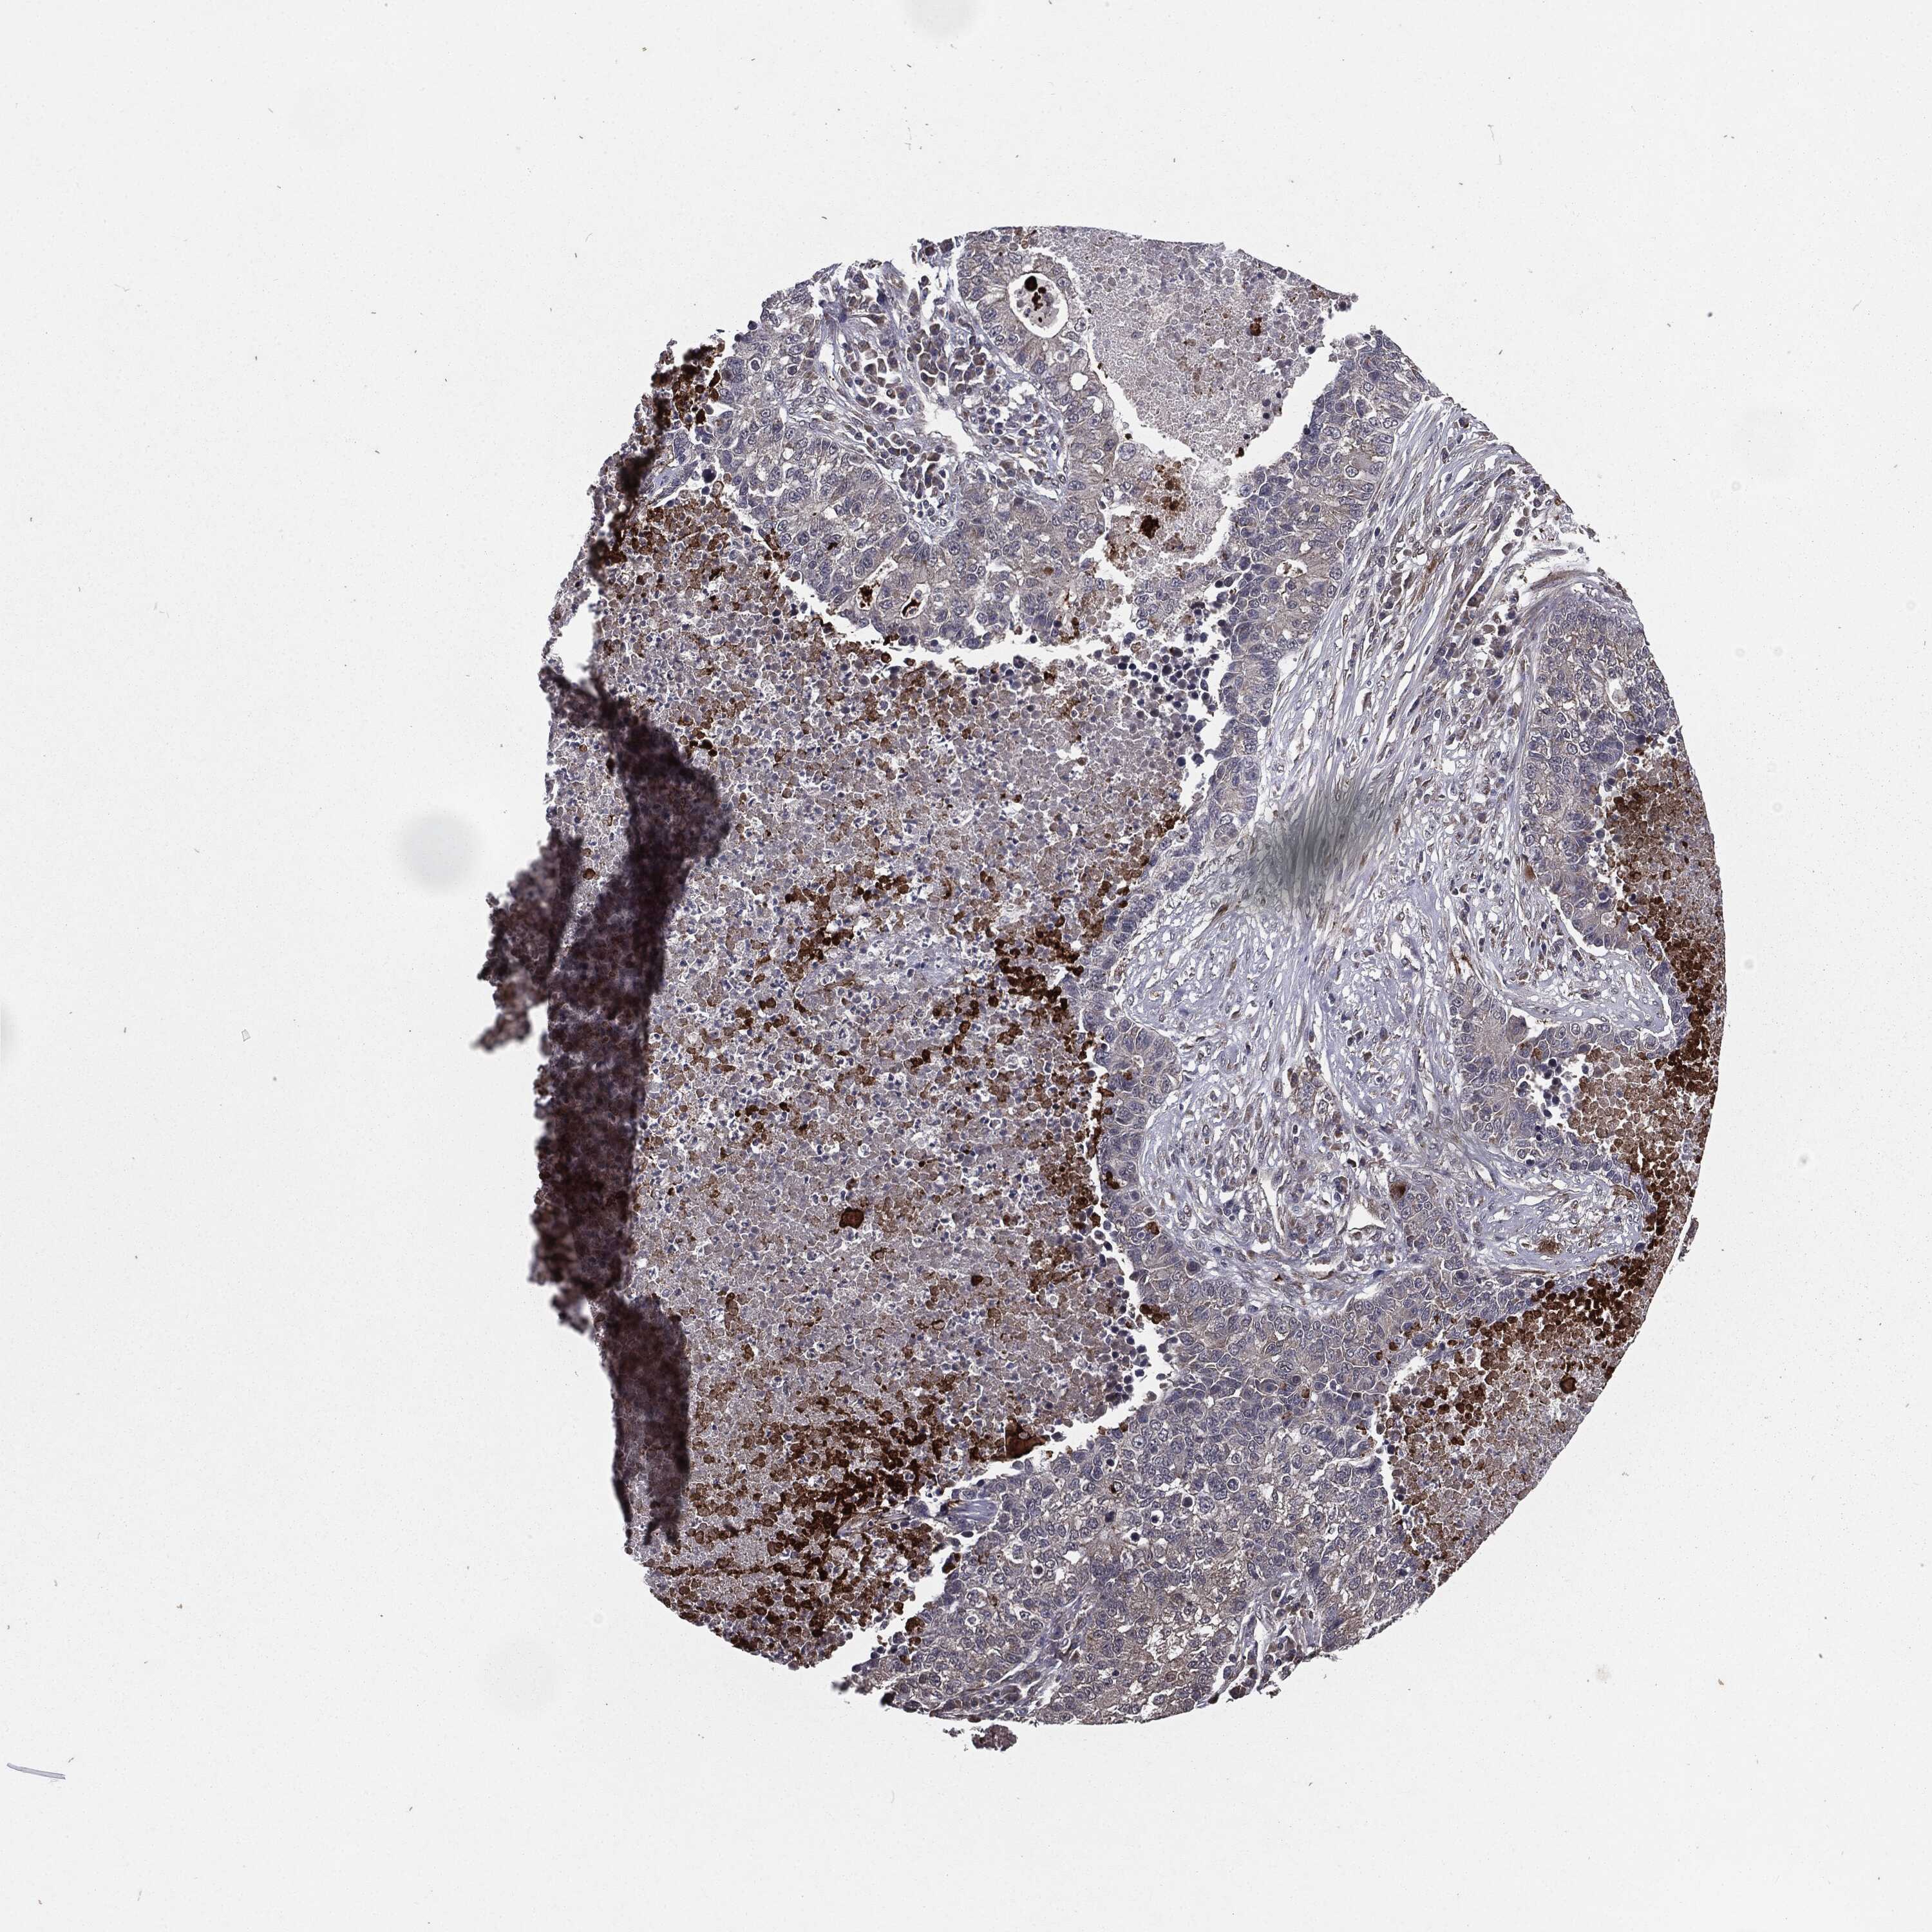

CANCER LUNG CANCER Show tissue menu

Lung cancer

Human cancer

WSB2 is not prognostic in Lung Adenocarcinoma (TCGA)

WSB2 is not prognostic in Lung Adenocarcinoma (validation)

WSB2 is not prognostic in Lung Squamous Cell Carcinoma (TCGA)